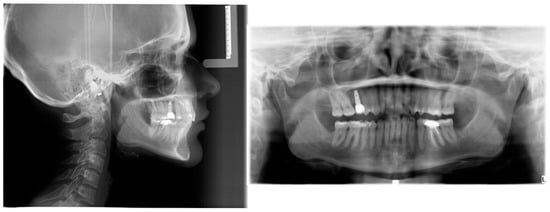

2.1. Pre-Treatment Records and Analysis

2.2. Pre-Treatment Diagnosis

2.3. Procedures and Appliances